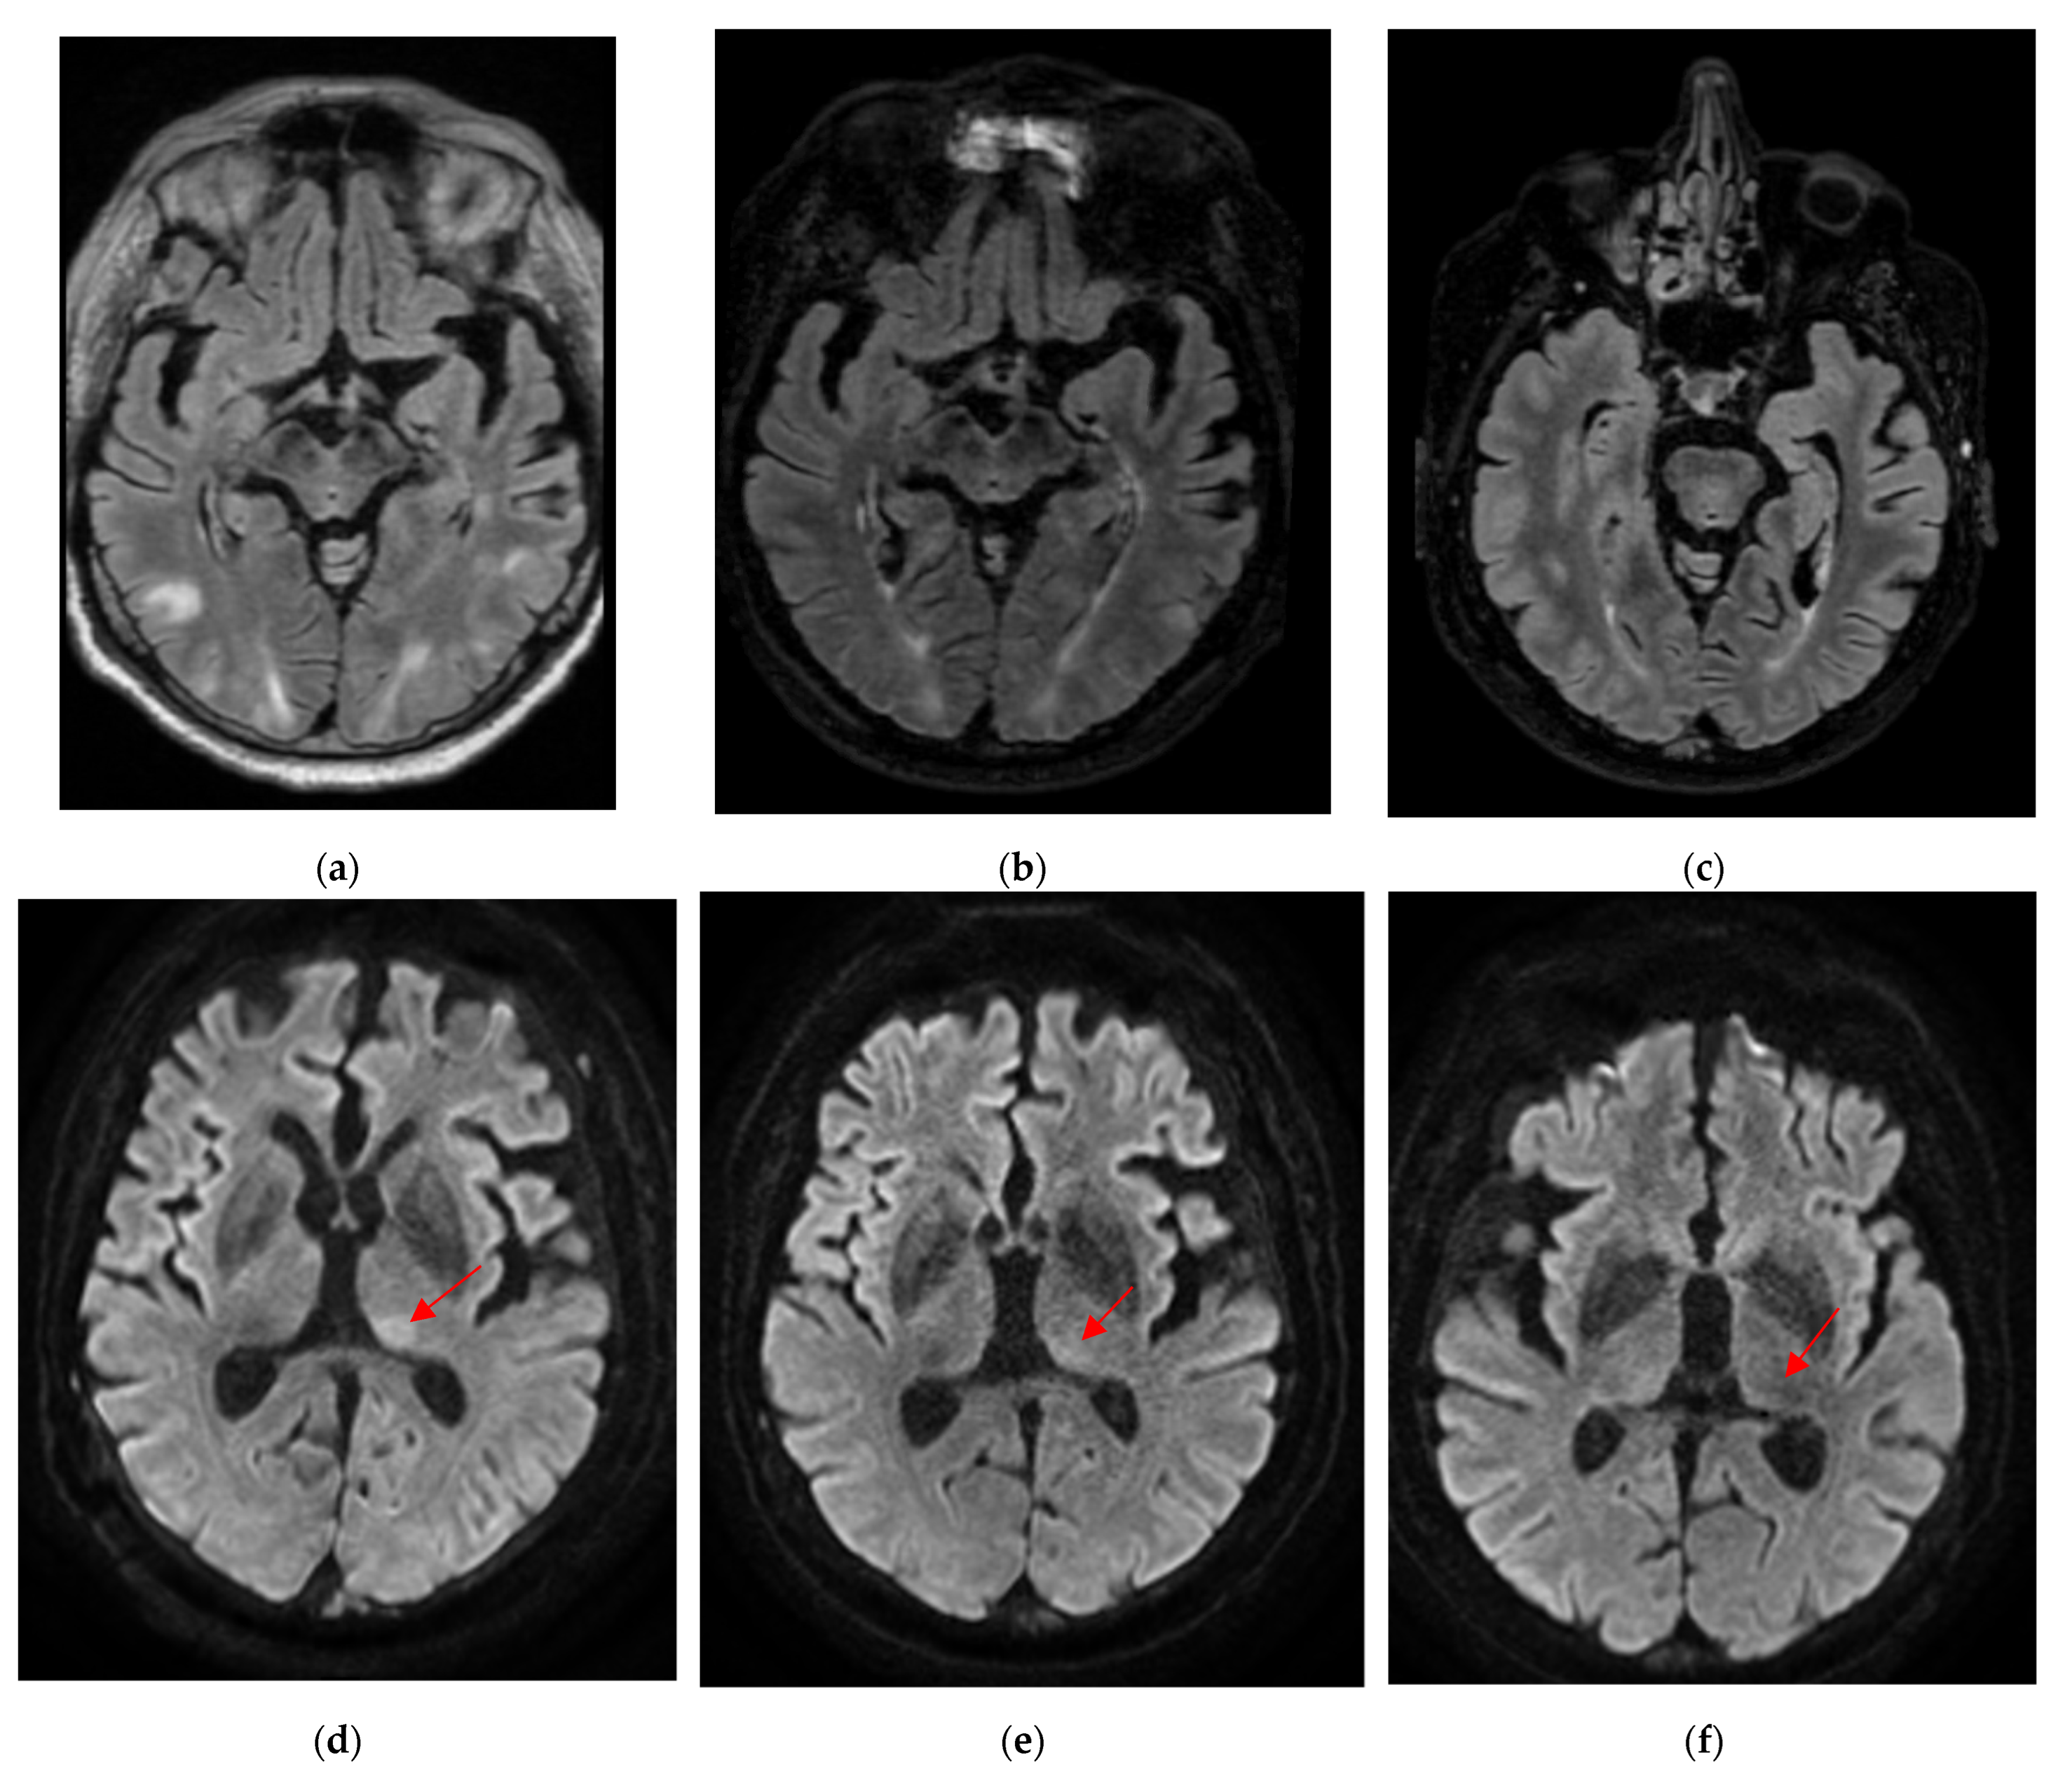

| Machine | Weighting | Sequence | TR | TE | Slice Thickness |

|---|---|---|---|---|---|

| Discovery MR 750w 3T Installed in 2012, 70 cm tunnel, 32 channels, 50 cm z-axisFOV, gradient 44 mT/m SR 200 T/m/s | T1 pre-contrast | 3D rapid gradient echo | 9 ms | 2.1 ms | 1 mm |

| T2-FLAIR | Turbo spin echo | 7002 ms | 118 ms | 1 mm | |

| DWI | EPI, two-b-values (0 and 1000 mm/s) | 3349 ms | 62.6 ms | 3 mm | |

| T1 post-contrast | 3D rapid gradient echo | 6.1 ms | 2.1 ms | 1 mm |